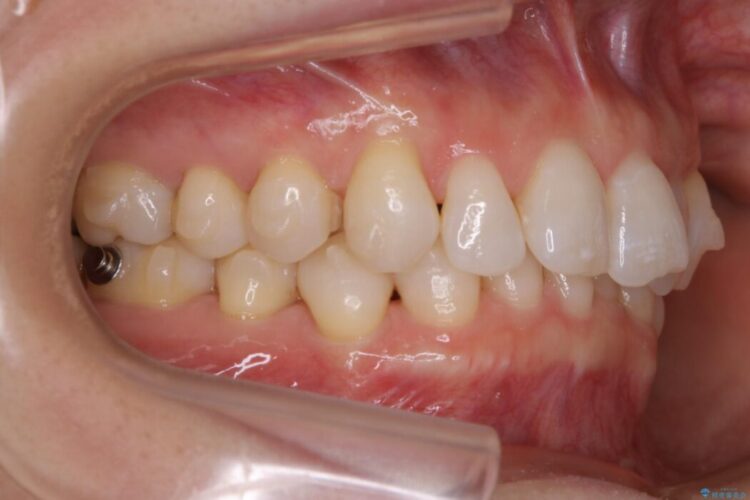

悪くなっている歯の放置はできないと判断しましたので、患者様と様々な治療プランを相談した上で、最終的に該当の歯は抜歯をして噛み合わせを改善し、その後インビザラインでの矯正治療を行うこととしました。

噛み合わせも改善され、一番最初の目的であった歯列もきれいに整いご満足いただけました。